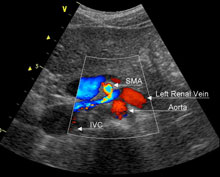

|

Figura 2. Schema cu raporturile vaselor renale stangi. Vena renala stanga trece prin pensa aortomezenterica, intre artera mezenterica superioara si aorta abdominala. Artera renala stanga este localizata posterior de vena renala. Prima imagine ecografica (dr. sus) este o vedere sagitala a aortei abdominale. Intre aorta si AMS se observa vena renala stanga. A doua imagine ecografica (dr. jos) este o ecografie Doppler transversala ce vizualizeaza raporturile anatomice dintre AMS, trunchiul celiac, aorta, VCI si vena renala stanga. |